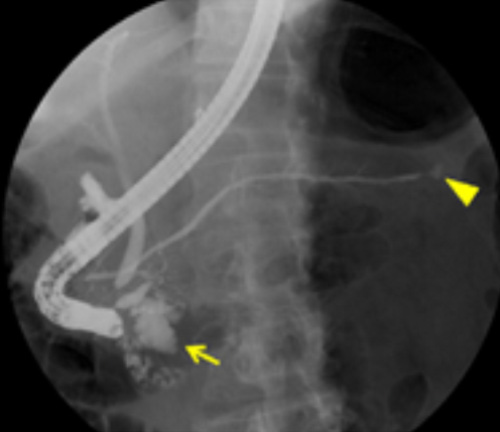

Ретроградная холангиопанкреатография (РХПГ) позволяет выявить кисты в поджелудочной железе

Ретроградная холангиопанкреатография